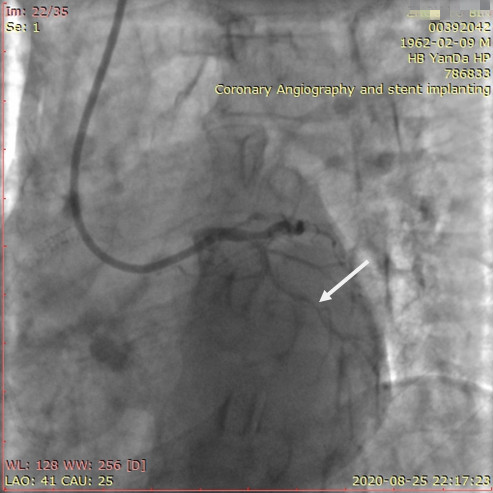

李先生足位術(shù)后影像

手術(shù)方案確定之后,在心血管內(nèi)三科趙景新主任、介入醫(yī)學(xué)科富孝晨主任的配合下,翟光耀主任親自擔(dān)任主刀,分別依次對李先生的三支動脈進行了完全血運重建。由于手術(shù)進展順利,李先生術(shù)中沒有任何癥狀,耐受良好,于是成功的將三支動脈“一站式”治療!術(shù)中,由于李先生左主干遠(yuǎn)端分叉處存在嚴(yán)重病變,翟光耀主任選擇國際指南推薦的DK-mini-Crush技術(shù),確保了分叉處兩支主干開口均萬無一失。據(jù)悉,DK-mini-Crush技術(shù)是目前冠脈分叉病變領(lǐng)域最為復(fù)雜及難以掌握的介入技術(shù)之一,對手術(shù)醫(yī)生經(jīng)驗、體力均提出了極大的挑戰(zhàn)。極為擅長復(fù)雜介入技術(shù)的翟光耀主任卻用嫻熟的技術(shù)確保了李先生手術(shù)的成功。

冠狀動脈嚴(yán)重鈣化合并狹窄病變是冠脈介入的一大難題,血運重建難度大,成功率低,并發(fā)癥發(fā)生率高,該例患者的成功救治標(biāo)志著我院冠脈介入水平又躍上了一個新的臺階。